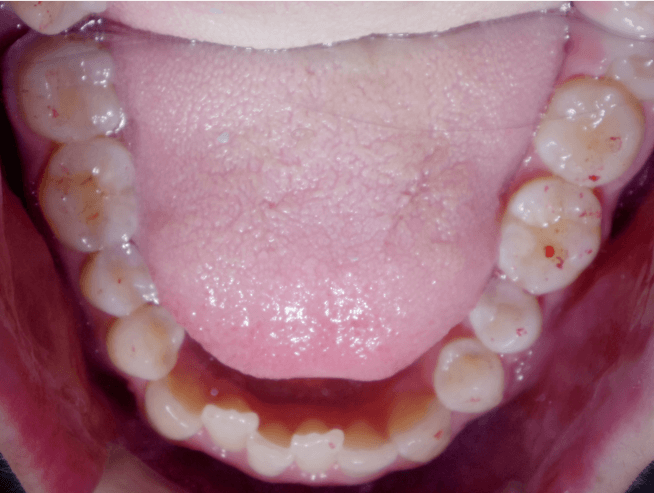

叢生(狭窄歯列弓)

BEFORE

AFTER

担当医コメント

下顎の歯が内側に倒れ狭窄歯列弓になっている。下顎を拡大することで下顎の歯列を整える計画をし、インビザラインで治療をする事にした。

治療の概要

年齢/性別

39歳 男性

主訴

下の歯の並びがガタガタなので、歯磨きがしにくいので治したいでした。

リスク

下顎の叢生改善時に歯肉退縮が起こる可能性がある

費用

82万円(矯正費用)

期間

8ヶ月

術前

術後